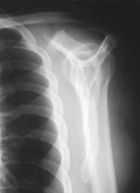

Case 6

27 year old male presents with pain in his left shoulder for about one year

Zoom image: Radiological image Radiological image.

Zoom image: Cell stain Cell stain.